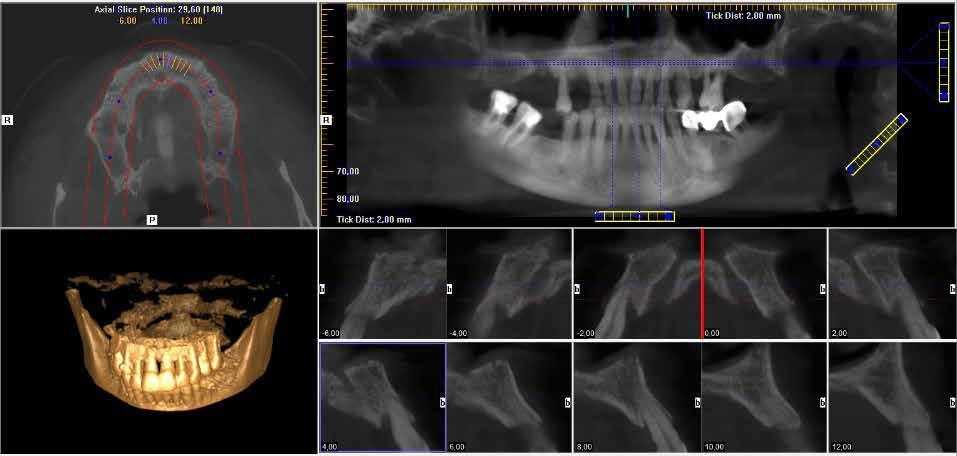

Páciens szelekció és tervezés A siker egyik kulcsa lehet, ha számításba vesszük a beavatko zások tervezésénél a páciensünk személyiségét, az elvárásait és az igényeit Sok olyan páciens van, aki ugyan szeretné pó toltatni a hiányzó fogait, de az egyszerűbb fogorvosi beavat kozásoktól is fél, egy műtétről pedig hallani sem akar Szá mukra meggyőzőbb lehet, ha a székben csak rövid időt kell eltölteniük, nincs csiszolás, nincs lebenyképzés és nincsenek Avarratokcikkben bemutatott páciens is hasonlóan érez� Évek óta megbízható betegem, jó szájhigiénével rendelkezik, zavarják a foghiányok, de ha lehetséges, elkerülné a műtéti beavat kozást Gyógyszert nem szed, nincs ismert allergiája, sem szisztémás betegsége� A bal alsó, második premoláris foga évtizedek óta hiányzik, ezt szeretné pótoltatni A CBCT felvé

tel alapján az implantáció elvégezhető kiegészítő csontpót lás nélkül, de az állcsontgerinc sorvadt, így csak egy keskeny implantátummal biztosítható a megfelelő pozicionálás Ilyen esetben fontos, hogy tartsuk az előre meghatározott pozíciót, egy kis eltérés is azt eredményezheti, hogy a buk kális vagy lingvális csontfal túl vékony lesz az implantátum mellett Egy 3,5 mm átmérőjű és 10 mm hosszú Megagen AnyRidge implantátumra esett a választásunk Érdemes fi gyelembe venni, hogy a 3,5 mm átmérőjű implantátum prog resszív menetemelkedéssel rendelkezik, és a legszélesebb menetnél 3,5 helyett 3,9 mm a tényleges átmérője, míg a teste csak 2,8 mm széles Ezzel az implantátummal kiváló primer stabilitás érhető el A műtéthez sebészi sablont terveztünk R2 Gate programmal, ezzel a tervezett pozíciót is tartani tudjuk, és a páciens számá ra is egy rendkívül gyors, lebenyképzéssel nem járó műtétet biztosíthatunk A tervezéshez szükségünk van egy intraorális scan-re, vagy egy hagyományos lenyomatvétel és modellké szítés után bescannelt modellre, valamint egy CBCT felvétel re� A CBCT felvételt és a digitális modell �stl file-ját importáljuk a programba, majd ezután a meglévő fogak és a CBCT fel vételen is látható lágyrész képletek segítségével, egymásra igazítjuk őket Ha a két file tökéletesen fedi egymást, akkor egy kompozit modellt kapunk, amelyen a szájüregi képletek, a fogak, valamint a csontkínálat és a csontban futó anatómi ai képletek is megtalálhatóak� A tervezés következő lépése, hogy alsó állcsont esetén kijelöljük a n alveoláris inferior-t, és ezt rögzítjük a digitális modellen Ezután kiválaszthatjuk az implantátum méretét, típusát, és pontosan beállíthatjuk a helyzetét A pozicionáláshoz segítséget nyújthat, akár egy technikus által előre elkészített, digitális wax up, akár a prog ramban generált wax up, mely a modellre vetíthető, így lát hatjuk például, hogy hol lenne a tervezett pótláson a rögzítő csavar helye Miután befejeztük a tervezést, lehetőségünk van a projektet exportálni a R2 Ware nevű programba, ahol néhány kattintás segítségével megkapjuk a sebészi sablon tervét, amelyet már küldhetünk is a 3D nyomtatóra Lehetőségünk van még egy olyan emulált modellt is exportálni, amelyen az implantátum hely zete is rögzítve van, mintha a már behelyezett implantátumról vettünk volna lenyomatot Ennek alapján, a labor már a műtétet megelőzően el tudja készíteni az ideiglenes pótlást, amely mini mális korrekcióval, a műtétet követően azonnal be is helyezhető A műtét A műtéti sablont a nyomtatás után ki kell dolgozni, ezt a tech nikus, vagy mi – ha saját nyomtatónk van – elvégezhetjük egy gipszmodell vagy egy nyomtatott modell segítségével Ezután mi 70%-os alkohololdatba áztattuk, mivel az általunk használt sablon anyaga nem alkalmas autoklávban történő Asterilizálásra�szájüregben ellenőriztük, hogy a sablon pontosan illeszke dik-e, ezt a sablonra készített, ellenőrző ablakok segítségével könnyen megtehetjük Az implantátum helyének előkészíté séhez speciális implantációs tálcát és fúrókat használhatunk� A R2 sablonhoz való fúrók tövét úgy alakították ki, hogy pon tosan illeszkedjen a nyomtatott perselybe, így nem kell szűkí tőt helyeznünk a sablonba Az implantáció során, sablon nélkül is fontosnak tartom a lassú fordulaton történő fúrást Sablon használatnál ez különösen fontos, hiszen a hűtővíz nehezebben jut el a hű tendő területre Ez csak megfelelően éles fúrókkal valósítható Ameg3,5 mm AnyRidge implantátum magja 2,8 mm, és a bal alsó második premoláris fog területen a csonttípus D2 volt, ezért a 3,3 mm átmérőjű Cortical Drill volt az utolsó fúró, amit hasz náltam az előkészítéshez� Az implantátum behelyezése egy speciális behajtóval törté nik, amely a kézidarabhoz és a nyomatékkulcshoz is csatla koztatható, a rajta lévő jelölések segítik az elfordulásgátló helyzetének és az implantátum mélységének a kontrollálását� Az AnyRidge-re jellemző, magas primer stabilitást itt is meg figyelhettük, a nyomaték a behelyezés során 45 Ncm-t ért el, ez alkalmassá tette az esetet arra, hogy azonnali, ideiglenes

2. ábra: A sablontervező programban az implantátum helyzete jól látható több különböző metszetből is.